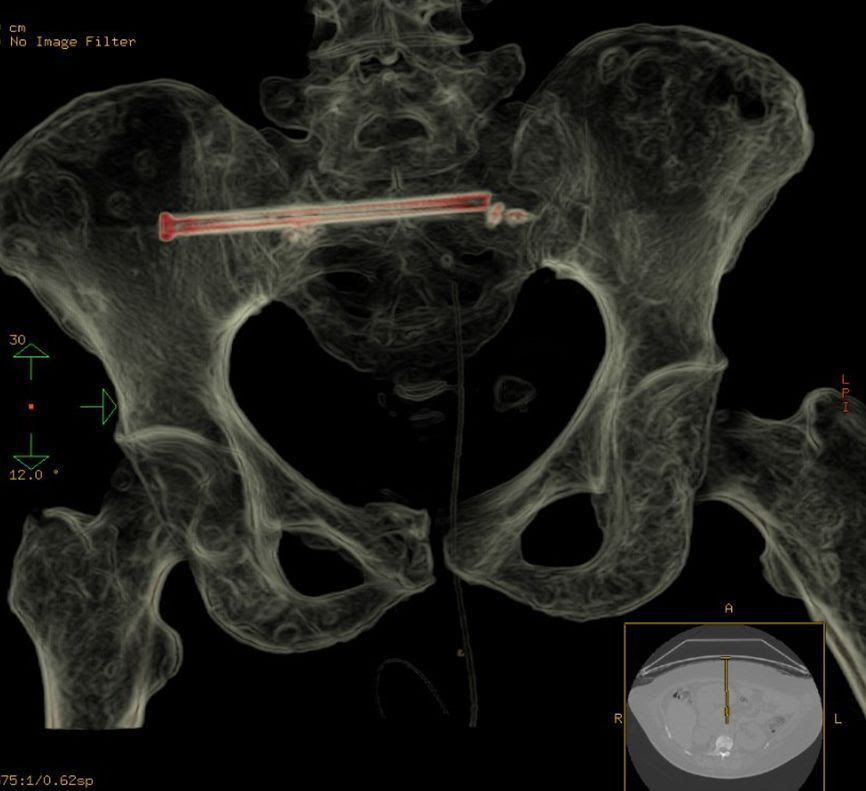

A specialized medical team at King Fahd Medical City in the capital Riyad succeeded Wednesday 12th October in repairing a fracture of the sacral bone in the pelvic area of a cancer patient by a metal screw using interventional radiology without surgery.

The team who includes bone-muscle radiology and interventional nonvascular radiology consultants found that the best way to treat the case was to stabilize the fracture to relieve pain and facilitate rehabilitation exercises.

The technique used began years ago and proved its success for patients who could not undergo surgery due to their critical conditions such as osteoporosis. The procedure is done through an incision in the skin of 2 to 3 mm under local or general anesthesia, and it takes about two hours to fully conclude each session.